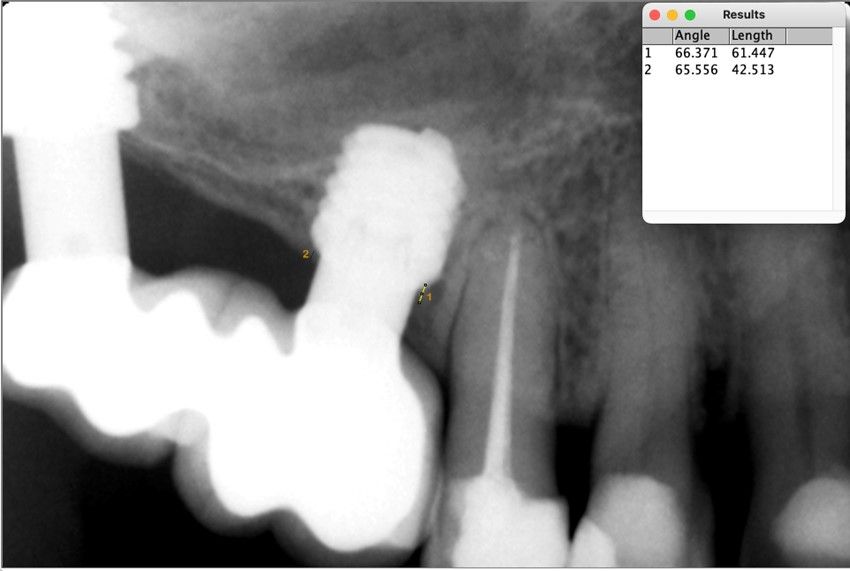

Material y método. Se ha llevado a cabo un estudio retrospectivo de pacientes tratados mediante implantes extracortos (5,5 y 6,5 mm de longitud) colocados mediante elevación transcrestal sin el uso de injerto. Como variables principales se han estudiado: la pérdida ósea crestal de los implantes y la ganancia en altura sobre el ápice. Como variable secundaria se ha estudiado la supervivencia de los implantes.

Resultados. Fueron reclutados 13 pacientes en los que se insertaron 30 implantes. Una vez insertados y cargados los implantes, la altura media final fue de 9,68 mm (+/- 2,66), lo que supone una ganancia promedio de 5 mm. A los 10 años, se observó una disminución media de la altura ósea ganada en los implantes en conjunto de 0, 29 mm (+/- 0,77). La media de la pérdida ósea mesial fue de 0,73 mm (+/- 0,75 mm) y la media de la pérdida ósea distal fue de 0,98 mm (+/- 1,2 mm). La supervivencia fue del 100%.

Material and methods. A retrospective study of patients treated with extra-short implants (5.5 and 6.5 mm in length) placed by transcrestal elevation without the use of a graft was carried out. The main variables studied were: the crestal bone loss of the implants and the gain in height above the apex. Implant survival was studied as a secondary variable.

Results.Thirteen patients were recruited and 30 implants were inserted. Once the implants were inserted and loaded, the mean final height was 9.68 mm (+/- 2.66), which represents an average gain of 5 mm. At 10 years, there was a mean decrease in the overall bone height gain of the implants of 0.29 mm (+/- 0.77). The mean mesial bone loss was 0.73 mm (+/- 0.75 mm) and the mean distal bone loss was 0.98 mm (+/- 1.2 mm). Survival was 100%.